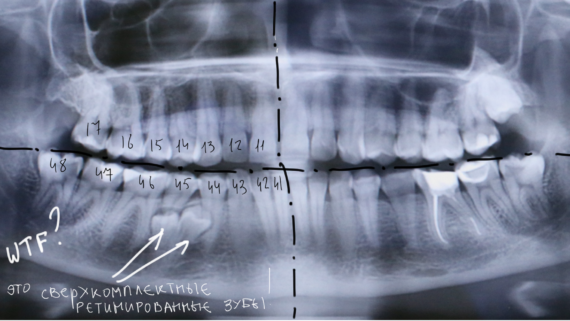

Однажды ко мне обратилась девочка по направлению от ортодонта. Принесла снимок:

Помимо аномального положения зуба мудрости есть еще одна проблема: восьмерка заблокировала седьмой зуб, в результате он не может прорезаться. В другой клинике ей предложили удалить два зуба, но она, по совету своего доктора, решила обратиться к нам в клинику.